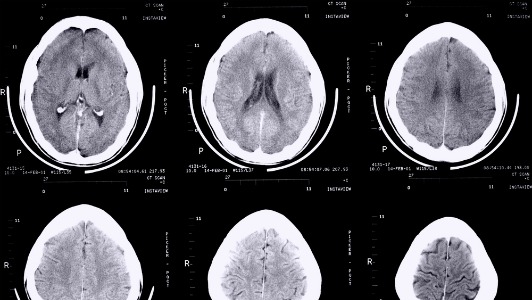

Le scanner cérébral confirme ces résultats: les seniors avec des taux élevés de trans présentaient une réduction significative de la taille du cerveau, en comparaison des autres sujets, et en particulier dans la région de l’hippocampe, un des sièges importants de la mémoire.